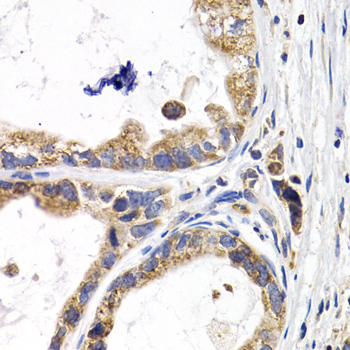

ApplicationWB, IHC